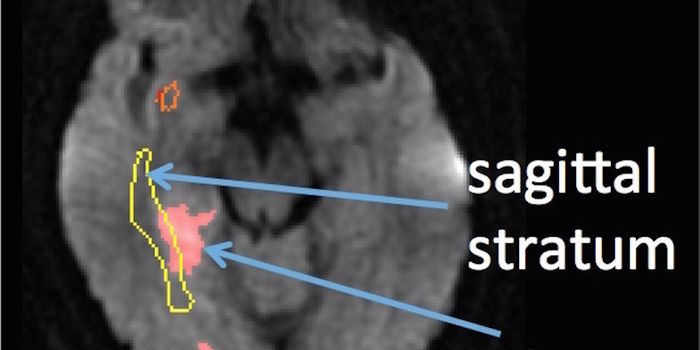

APR 16, 2015ImmunologyAbout 15% of patients with Lyme disease develop peripheral and central nervous system involvement, often accompanied by ...